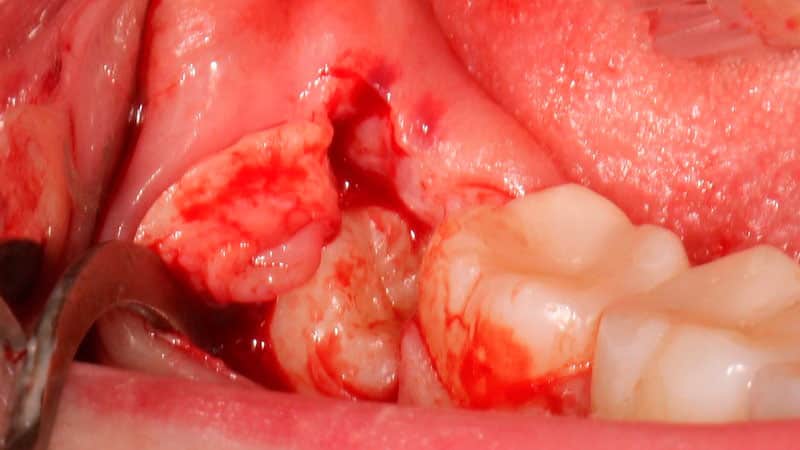

Как удаляют «мудрые» моляры

Сложное удаление зуба мудрости